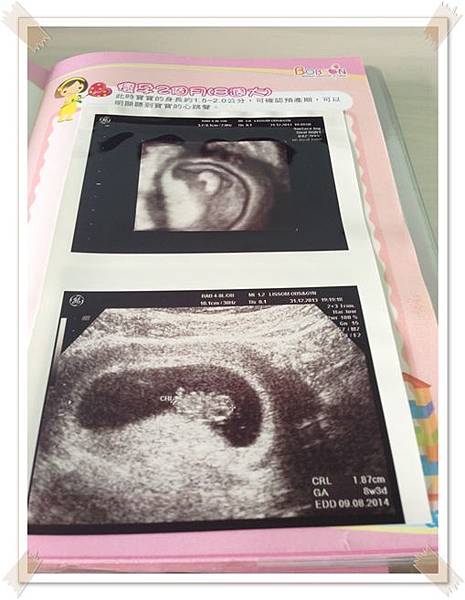

除了懷孕初期有比較常照超音波之外, 從懷孕8週起到28週都是1個月產檢一次

婦產科醫生幫我照了超音波順便詢問我之後產檢是否要在此

我說是醫生便約了下次12W回診的時間

婦產科的超音波設備是4D的,, 只是每次醫生印了一堆給我,我都搞不清楚是身體哪個部位